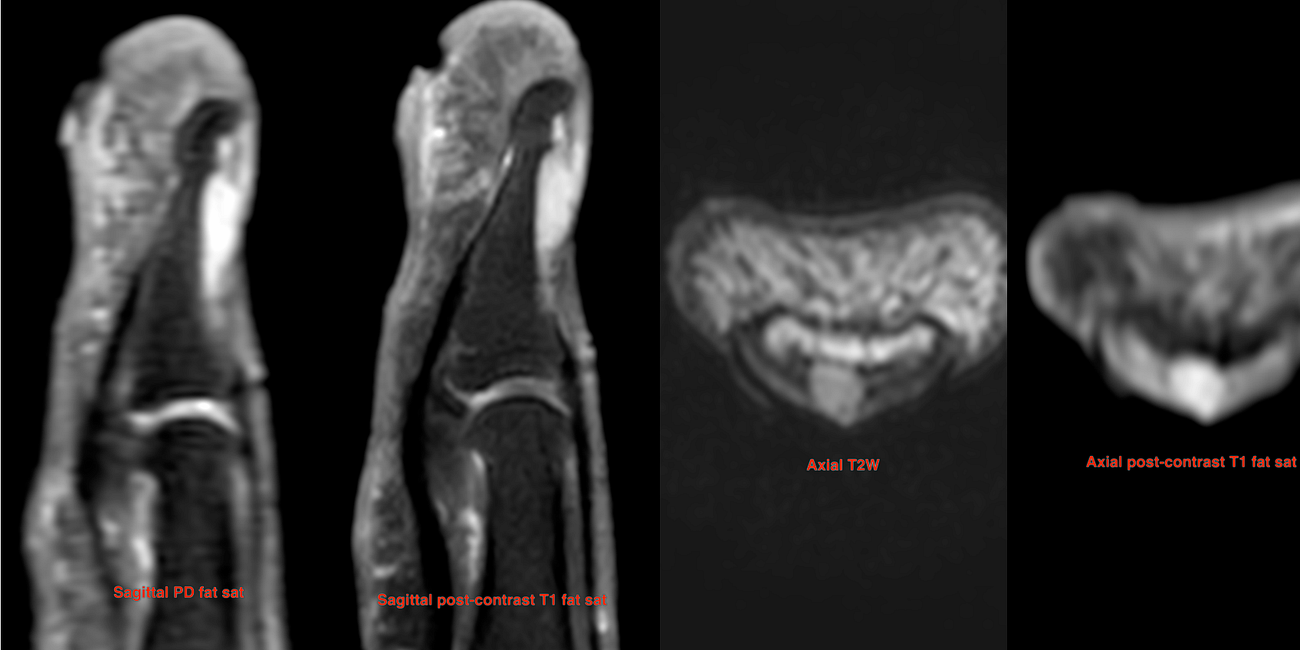

Case 53: A Throbbing Finger